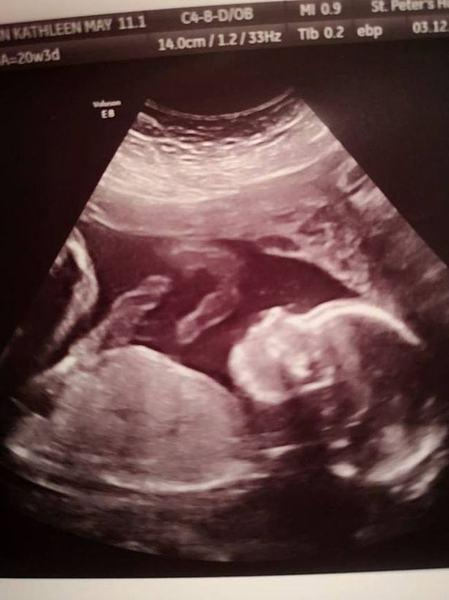

Pacientele au fost Bethan Simpson, o tânără de 26 de ani și fetița ei nenăscută. Potrivit ziarului The Mirror, doctorii au descoperit la analize, în cea de-a 20-a săptămână de sarcină, că micuța are spina bifidă, un defect de închidere de os la coloana vertebrală, care îi putea afecta capacitatea copilului de a merge.

„Și eu, și bebelușul am trecut prin teste de lichid amniotic, RMN și nenumărate ecografii”, a spus mama fetiței, potrivit The Mirror.